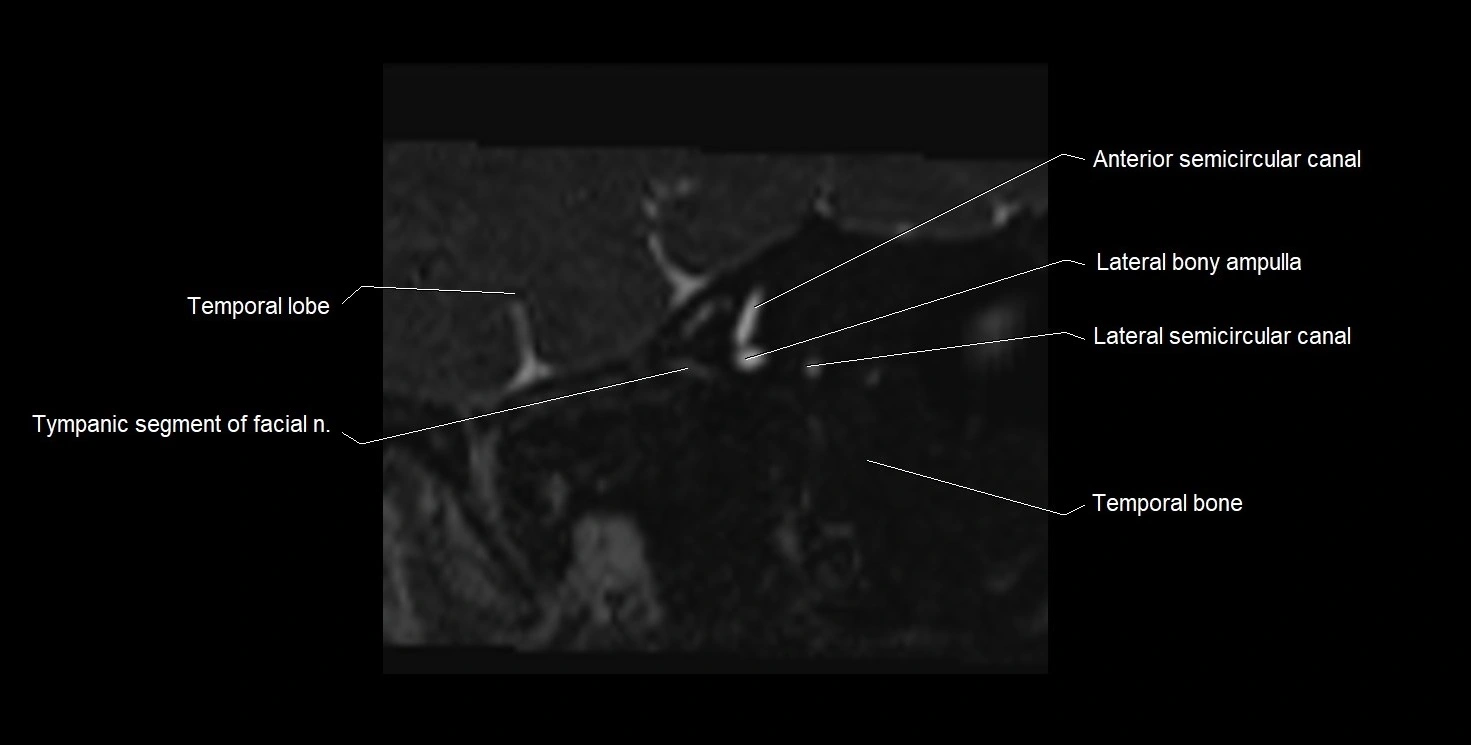

MRI Appearance

• The abducens nerve is a small, thin, linear structure

• Best visualized on high-resolution T2-weighted 3D MRI sequences (e.g., FIESTA or CISS)

• Seen as a hypointense (dark) line running from the brainstem at the pontomedullary junction, traversing the prepontine cistern, and entering Dorello’s canal under the petrosphenoidal ligament, then into the cavernous sinus, and finally the orbit

• May be challenging to visualize in standard MRI due to its small size

• Pathology may be inferred by absence, displacement, or enhancement of the nerve